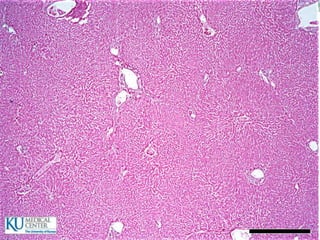

ESTÓMAGO

 2 a 3 L

Otras capas del estómago

 Submucosa

 Muscular

 Serosa